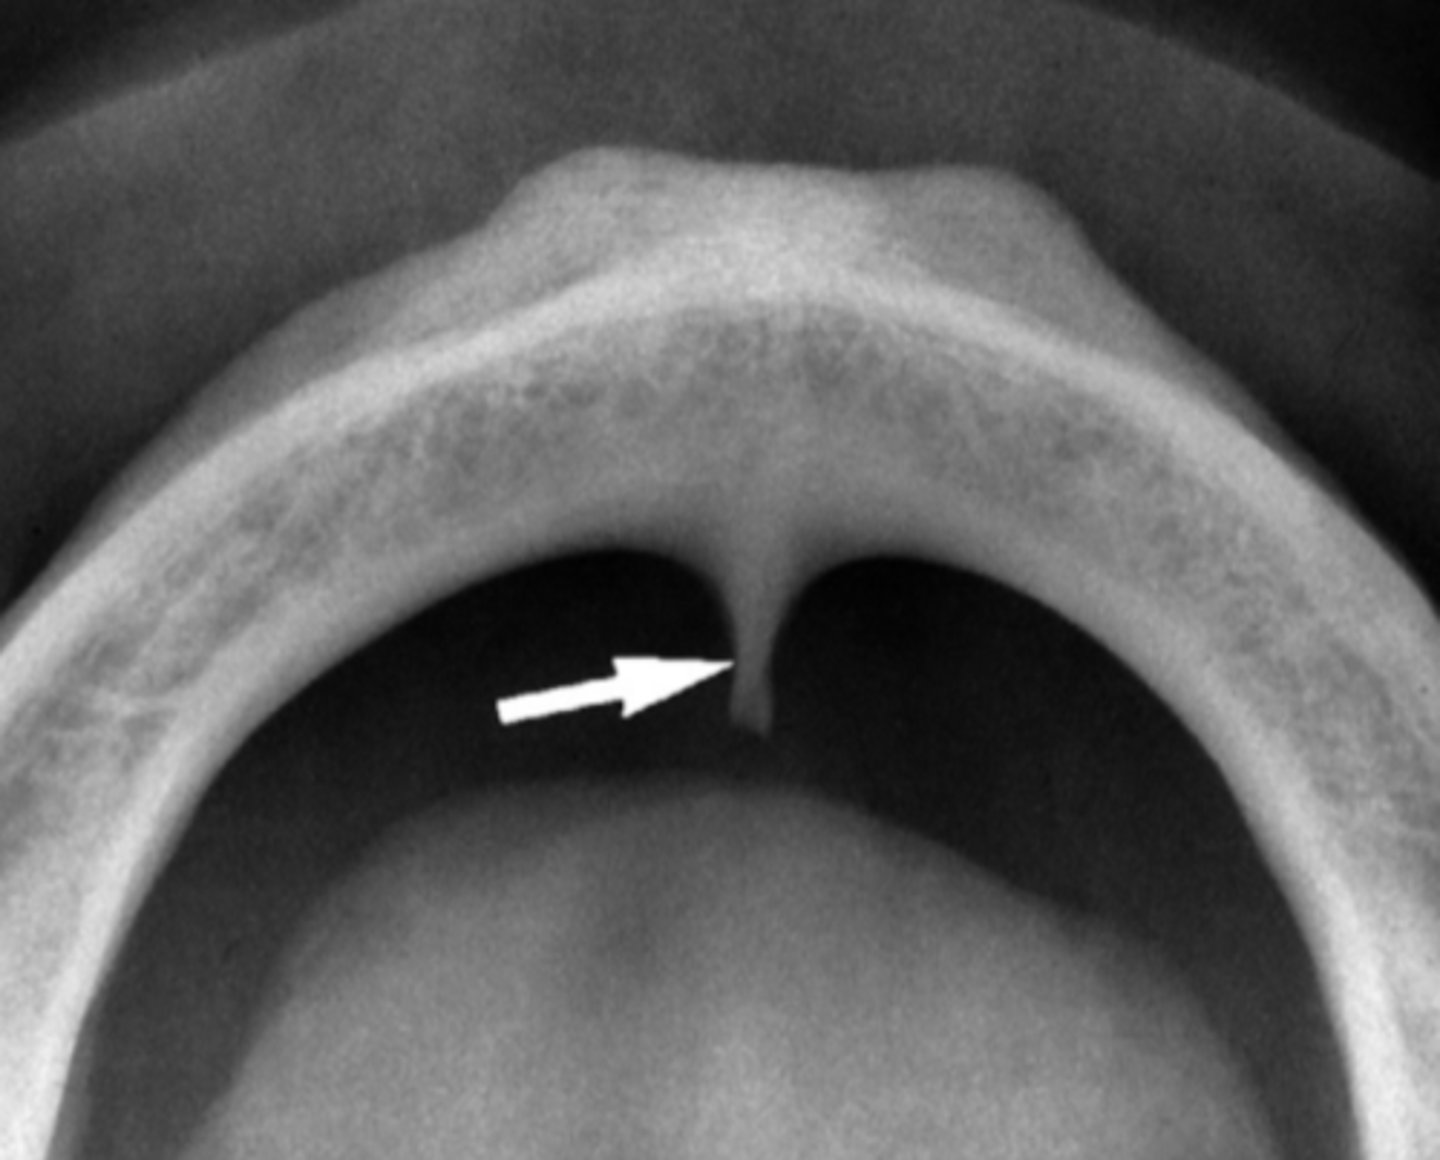

Superior foramina of the nasopalatine duct

Name the two round radiolucencies indicated.

<p>Name the two round radiolucencies indicated.</p>

Incisive foramen

Identify the structure

<p>Identify the structure</p>